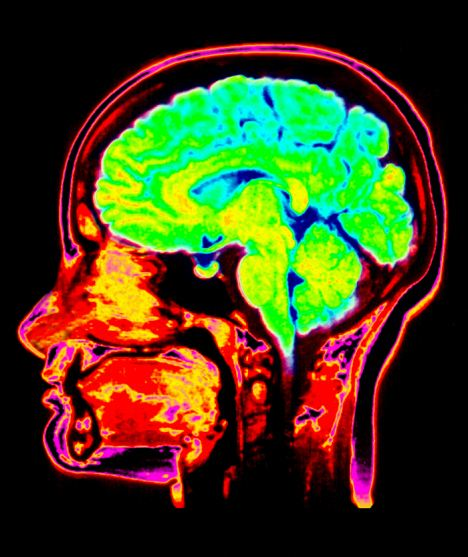

គួរយល់ដឹង ៖ នរណាថា Perpetually 29 អាចនឹងជាដំណឹងអាក្រក់? បើយោងទៅតាមអ្នកសិក្សាស្រាវជ្រាវបានអោយដឹងថា ពួកគេបានរកឃើញ Developmental Clock នៅក្នុងខួរក្បាលរបស់មនុស្ស ខណៈពេលដែលវាមានអត្តប្រយោជន៍ ក្នុងការបញ្ជាក់ពីអាយុរបស់បុគ្គលណាមួយ ដែលវាមានភាពត្រឹមត្រូវ ជាក់លាក់ រហូតដល់ទៅ 92% ឯណោះ។

គួរបញ្ជាក់ផងដែរថា បើយោងទៅតាមសម្តីរបស់លោក Timothy Brown ដែលបានមកពី Universityof Californis, San Diego School of Medicine បាននិយាយបញ្ជាក់អោយដឹងថា ៖ ពួកយើងបានរកឃើញនូវ Developmental Clock នៅក្នុងខួរក្បាល ពោលវាគឺជា សញ្ញាណជីវសាស្រ្តមួយ ដែលអាចចាប់យក ក៏ដូចជាធ្វើការវិភាគទៅលើអាយុកាលរបស់បុគ្គលម្នាក់ៗ។

លើសពីនេះទៅទៀត គាត់បានបន្ថែមផងដែរថា ក្រោយពីមានការប្រើប្រាស់បច្ចេកវិទ្យាមួយដែលអោយឈ្មោះថា MRI ក្នុងការ scan ខួរក្បាលក្នុងចំណោមមនុស្ស 885 នាក់ដែលមានអាយុពីចន្លោះ 3 ទៅ 20 ឆ្នាំ បានរកអោយឃើញថា វាមានប្រសិទ្ធភាពខ្ពស់ក្នុងការវិភាគអាយុកាលរបស់បុគ្គលម្នាក់ៗ ពោលគឺ វាមានភាពត្រឹមត្រូវនឹងច្បាស់លាស់រហូតដល់ទៅ 92% ឯណោះ៕